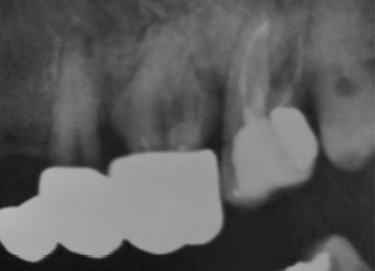

Abstract Image